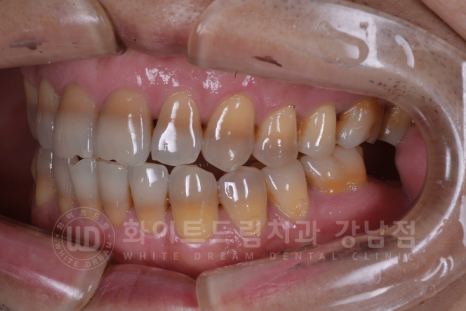

치료 전, 환자분 치아 상태.

- 어금니(37,17,16번 치아)는 현재 본원에서 UV 임플란트 치료 중입니다. ^^

강남역 인근 치과, 테트라사이클린 변색 치료 전

테트라사이클린 변색은 일반 누렁 니와 다르게 심하게 눈에 띄기에 치아 스트레스가 심하신 분들이 많습니다.

오늘 소개해 드릴 환자분도 40대의 남성분이셨는데요.

치아 변색을 한참 고민을 하다가 치료를 받기로 결심을 하신 분이었습니다.